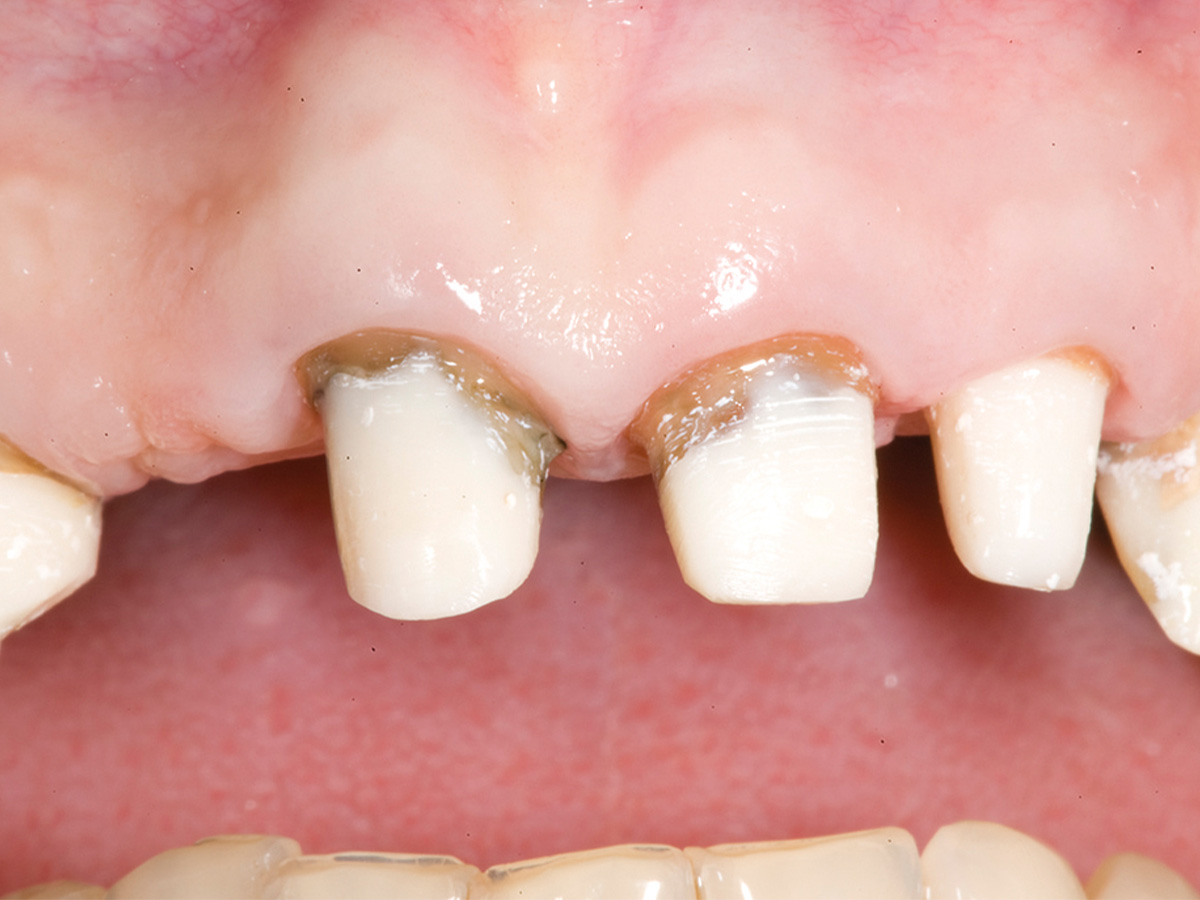

Abbildung 9

6 Monate post-OP nach Freilegung. Zu beachten ist der Alveolarkamm im Gegensatz zum Ausgangsbefund.